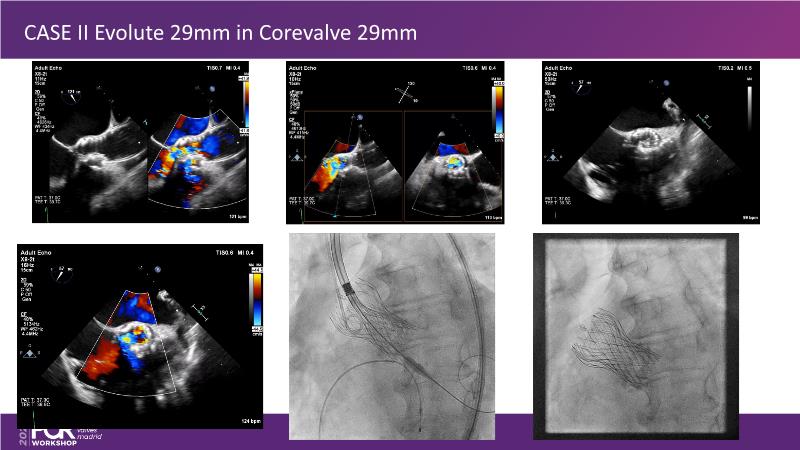

Explore cutting-edge transcatheter valve interventions for mitral and aortic valve disorders, including valve-in-valve procedures and management strategies for paravalvular leakages, and learn about diagnosing and treating mitral annular calcification and transcatheter options in infective endocarditis.

- To get tips and tricks for guidance of transcatheter intervention